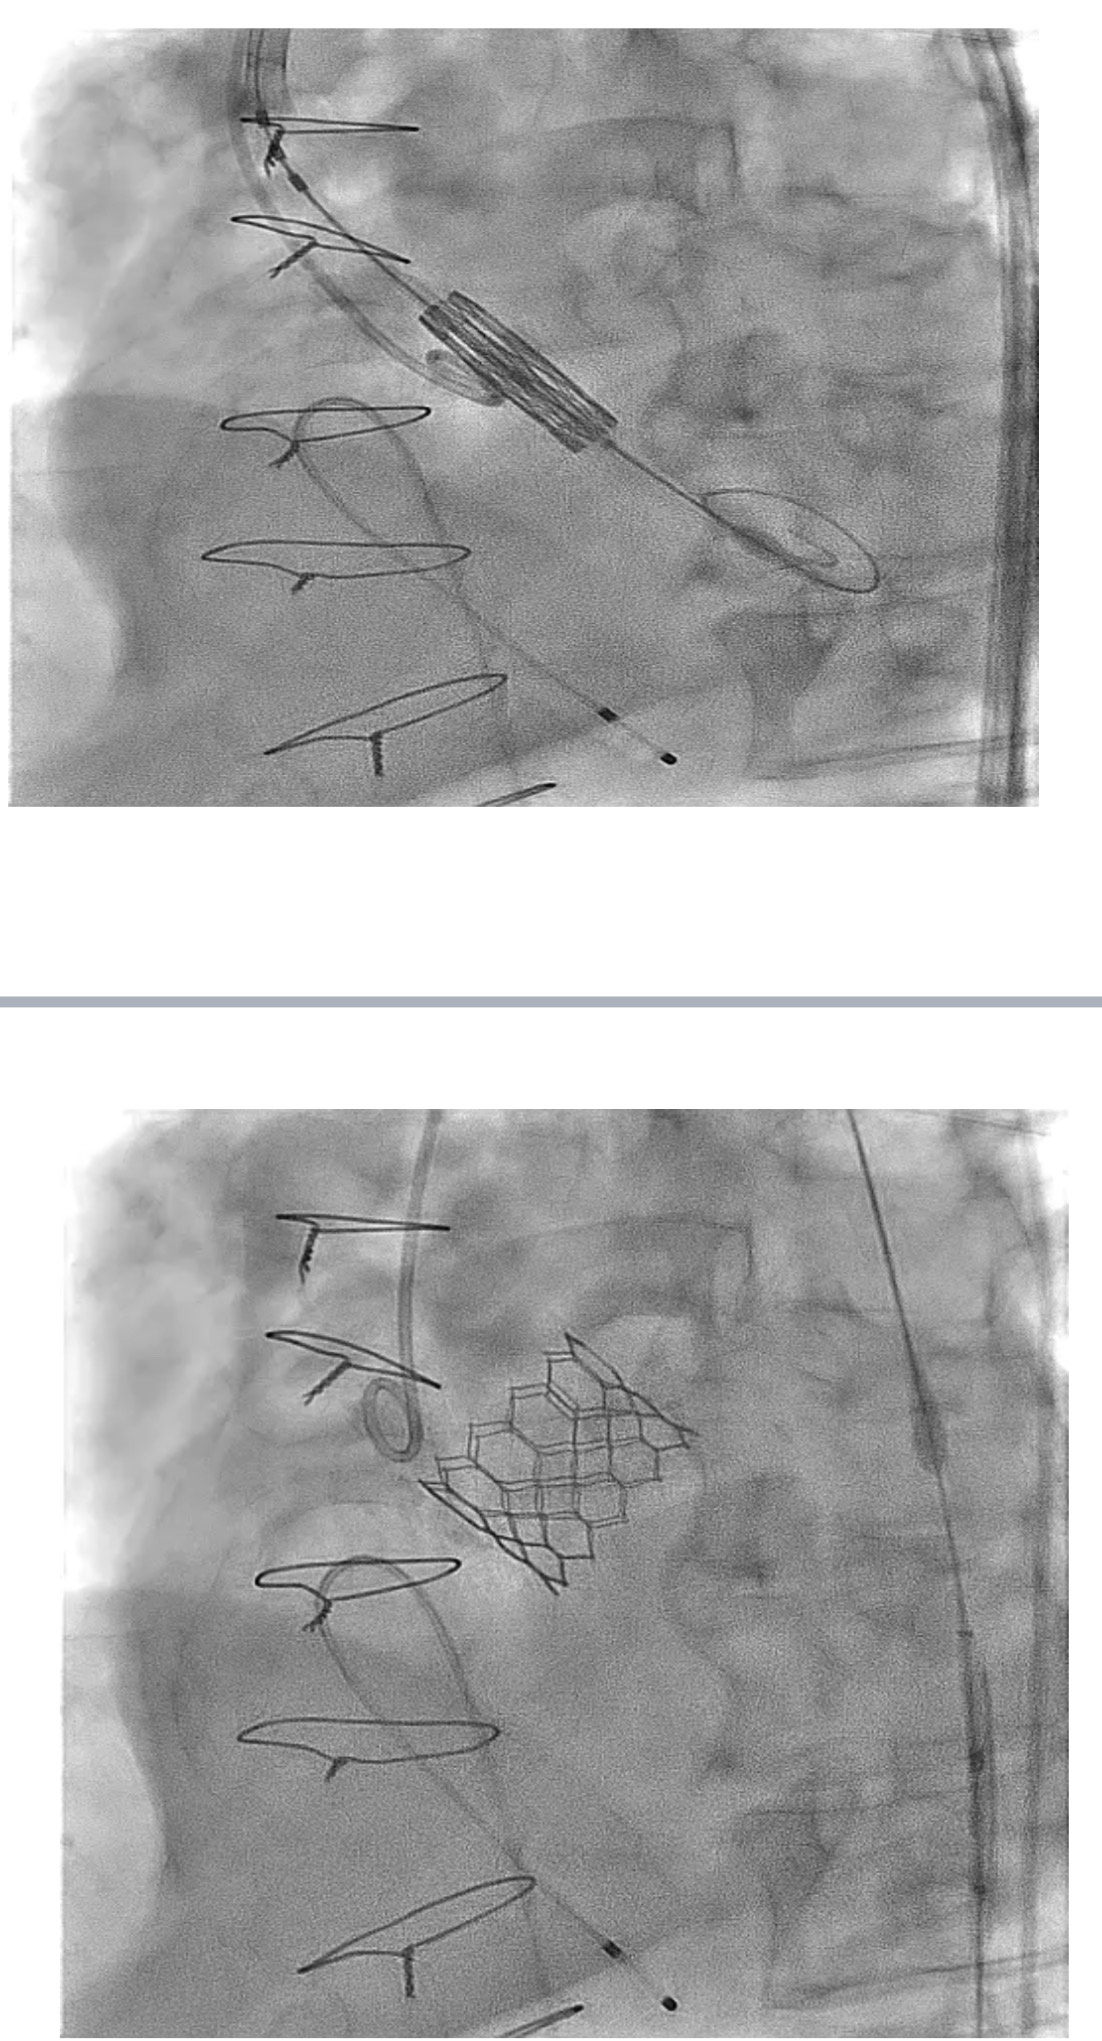

Following informed consent, the TAVI procedure was performed in the hybrid catheterization lab via a standard transfemoral approach. Femoral sheaths were inserted under fluoroscopic and ultrasound guidance, and the aortic valve was crossed with a Confida wire placed in the left ventricle. A pigtail catheter was positioned in the non-coronary cusp, and a baseline aortogram was performed using Gadobutrol administered via an automated injector. A 29 mm Sapien 3 Ultra valve (Edwards Lifesciences, Irvine, California) was deployed after confirming its position with a Gadobutrol aortogram. The image quality was comparable to iodinated contrast media (ICM), and the procedure was successfully completed without any adverse reactions to Gadobutrol.

Post-TAVI aortography confirmed proper valve positioning with only a trivial paravalvular leak (PVL). The access sites were successfully closed using ProGlide and Angio-Seal devices. A total of 50 cc of Gadobutrol was used. Pre-discharge transthoracic echocardiography (TTE) confirmed good transcatheter heart valve (THV) positioning, no PVL, and a peak gradient of 6 mmHg. Renal function tests performed one week post-procedure showed no deterioration, with a creatinine level of 156 µmol/L.

Following informed consent, the TAVI procedure was performed in the hybrid catheterization lab via a standard transfemoral approach. Femoral sheaths were inserted under fluoroscopic and ultrasound guidance, and the aortic valve was crossed with a Confida wire placed in the left ventricle. A pigtail catheter was positioned in the non-coronary cusp, and a baseline aortogram was performed using Gadobutrol administered via an automated injector. A 29 mm Sapien 3 Ultra valve (Edwards Lifesciences, Irvine, California) was deployed after confirming its position with a Gadobutrol aortogram. The image quality was comparable to iodinated contrast media (ICM), and the procedure was successfully completed without any adverse reactions to Gadobutrol.

Post-TAVI aortography confirmed proper valve positioning with only a trivial paravalvular leak (PVL). The access sites were successfully closed using ProGlide and Angio-Seal devices. A total of 50 cc of Gadobutrol was used. Pre-discharge transthoracic echocardiography (TTE) confirmed good transcatheter heart valve (THV) positioning, no PVL, and a peak gradient of 6 mmHg. Renal function tests performed one week post-procedure showed no deterioration, with a creatinine level of 156 µmol/L.